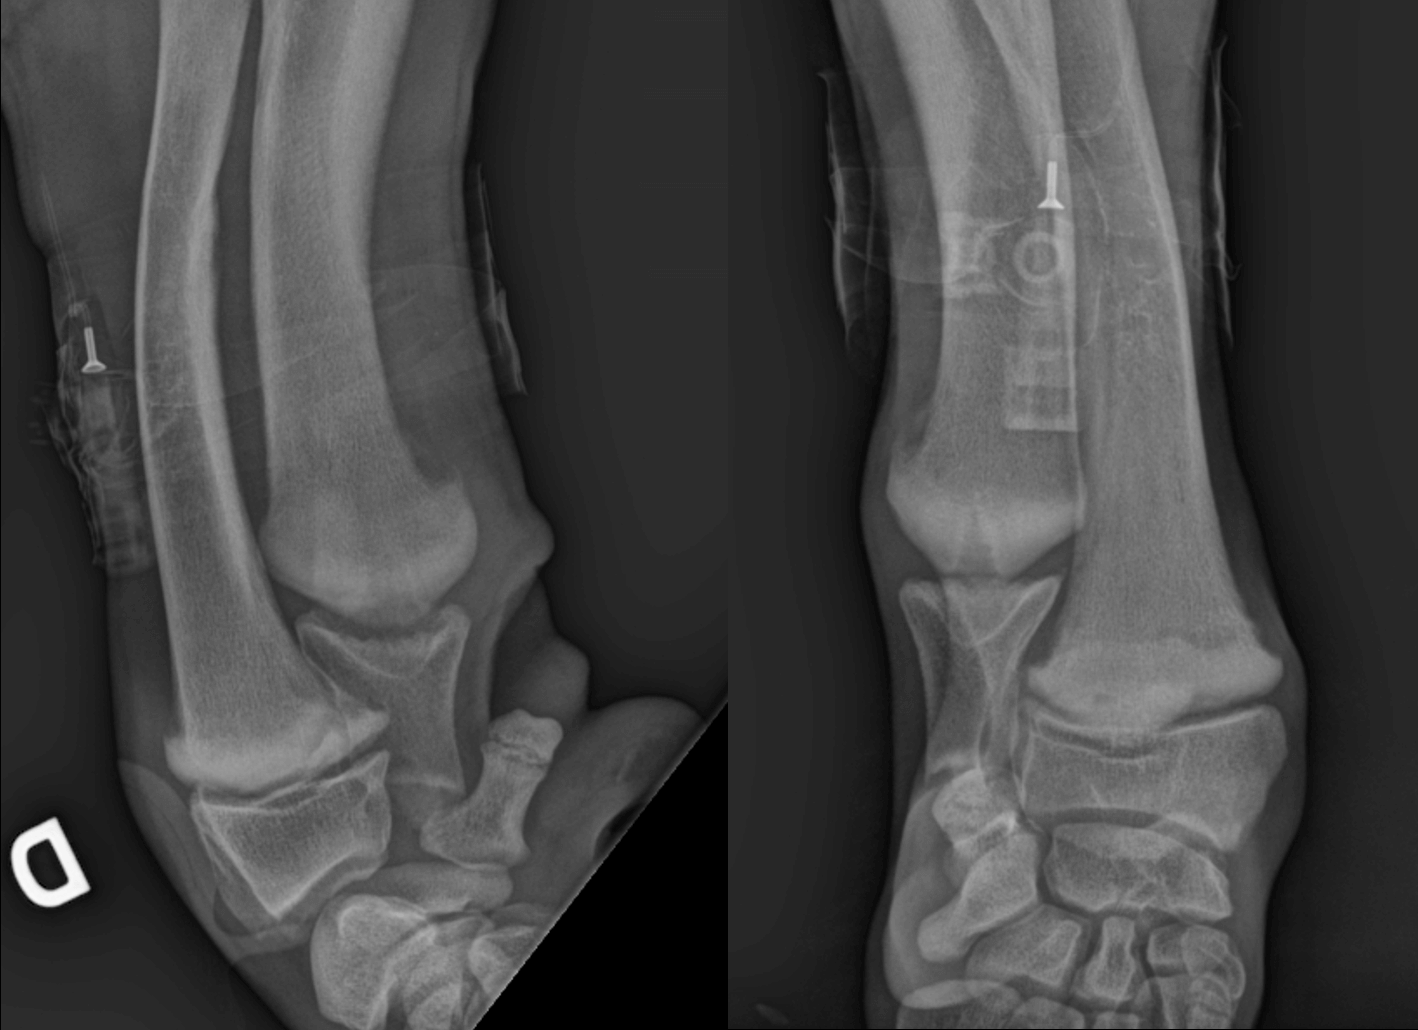

- L'examen radiographique, qui est crucial pour confirmer le diagnostic.

Les radiographies révèlent des signes pathognomoniques, notamment une ligne radiotransparente dans la métaphyse, parallèle à une zone étroite de densité accrue immédiatement adjacente à la physe. Il est important de noter que ces changements radiographiques peuvent ne pas être visibles avant 48 à 72 heures après l'apparition des premiers signes cliniques.Dans les stades plus avancés, on peut observer une prolifération périostée et endostée, ainsi qu'un élargissement excessif des métaphyses, créant un aspect caractéristique en "collerette" osseuse.Le diagnostic différentiel doit inclure l'hyperparathyroïdie nutritionnelle secondaire, la polyarthrite septique, les traumatismes, les noyaux cartilagineux retenus et l'ostéopathie hypertrophique.

Sclérose au niveau de la métaphyse du radius et de l'ulna

Mise en évidence d'une ligne radio-transparente irrégulière en regard de la métaphyse, longeant le cartilage de croissance et séparée de celui-ci par une bande radio-opaque.